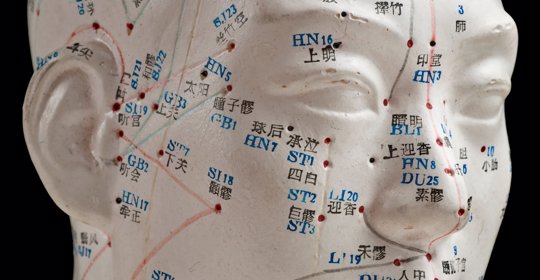

風邪致病:頭痛、汗出、惡風處理方式